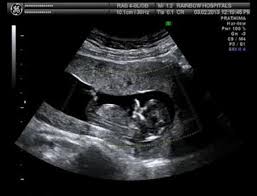

The scan is usually performed transabdominally but in a few cases it may be necessary to do the examination transvaginally. A dating scan is an ultrasound examination which is performed in order to establish the gestational age of the pregnancy. Pairing the nt scan with a blood test lowers the likelihood of a false positive. Dating scans also reveal other important information such as: Together, both these tests are known as the combined screening test. A dating scan is an ultrasound scan carried out at around 12 weeks of pregnancy, that's used to work out your due date. The number of fetuses and gestation sacs. A dating scan is usually done to check how many weeks.

This means the baby tests with a high risk yet does not end up having down syndrome. A dating scan is an ultrasound scan carried out at around 12 weeks of pregnancy, that's used to work out your due date. My partner and i went off to get the 12 week scan yesterday, only to be told afterwards that the baby has a higher than normal nuchul translucency of 3.5mm. Between 11 weeks and 13 weeks plus six days of pregnancy Increasingly, though, doctors and midwives are offering women a dating scan before their nt scan.

#18 moments, feb 17, 2012. Usually the scan is done through your abdomen but occasionally the nuchal translucency can only be seen by inserting a probe into the vagina. Is offered between 11 and 14 weeks of pregnancy This scan is also used to check that your baby's development is on track and is often part of combined screening for genetic variations, such as. It might need to be done alone, or it might be able to be done while you're having your dating scan. Regarding the actual dating of my pregnancy, the hospital has labeled me currently at 12 weeks based on the size of fetus at 6cm. The nuchal scan (nt scan) is a screening done during an antenatal ultrasound to measure the amount of fluid at the base of your baby's neck. The nuchal translucency scan (also called the nt scan) uses ultrasound to assess your developing baby's risk of having down syndrome (ds) and some other chromosomal abnormalities, as well as major congenital heart problems. If i wa 13 weeks at dating scan does this then mean baby only really 11 weeks old? A dating scan will be done so you know what your new due date (estimated date of delivery) is and when to rebook for your nt scan. Between 11 weeks and 13 weeks plus six days of pregnancy A dating scan might be recommended before 12 weeks to confirm your due date if you are unsure of your last menstrual period or your date of conception. You may be offered a dating scan between eight and 10 weeks.